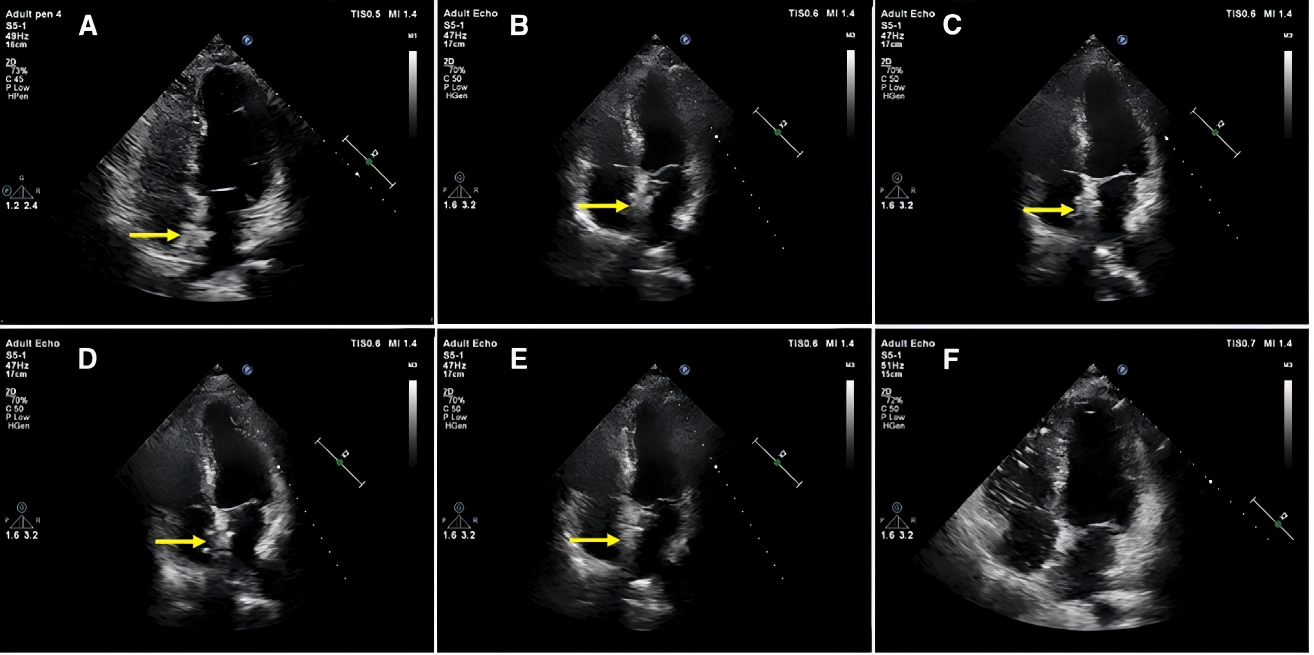

经胸超声心动图显示,术后6个月新型可降解封堵器在心内表现为突出的高回声区。随访至24个月,该封堵器与周围心内膜水平一致。左盘高回声区降解比例在术后1、3、6、12和24个月分别为92.59%、83.41%、64.62%、16.41%及0%;右盘分别为92.43%、83.44%、66.26%、17.37%及0%。各随访时间点,左右盘降解比例无统计学差异。到植入24个月时,代表新型可降解封堵器的高回声区在所有患者超声下均未在观察到,提示封堵器已完全降解。

TTE下生物可降解封堵器在术后24个月随访期间的形态变化。

黄色箭头所示为生物可降解封堵器。出院前(A)、术后1个月(B)、3个月(C)、6个月(D)、12个月(E)及24个月(F)随访时均进行了经胸超声心动图四腔心切面检查。术后24个月时,封堵器已完全降解。